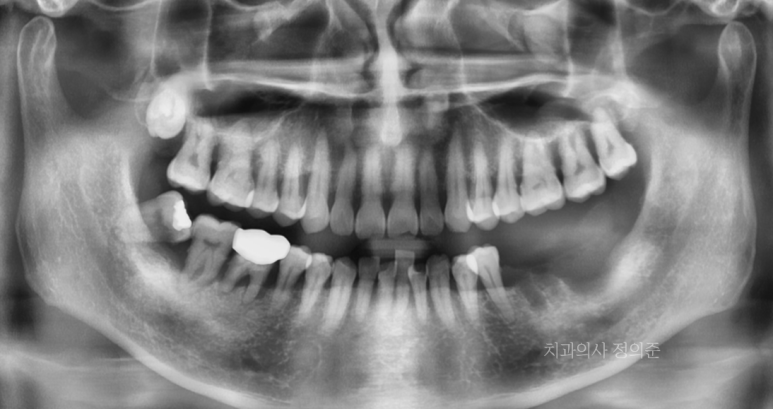

타치과에서 발치하시고 1주일 뒤에 내원하셨을 때의 파노라마 (좌측 사진)

첫 내원 당시의 왼쪽 아래 어금니 부위의 상태 (우측 사진)

2023. 7

내원 당시 왼쪽 아래 큰 어금니들을 발치하신 상태셨고,

1주일 정도 밖에 되지 않아 아무래도 잇몸은 회복 과정에 있는 상태였습니다.

정확한 진단과 치료 계획 수립을 위하여 CT 촬영을 진행하였습니다.